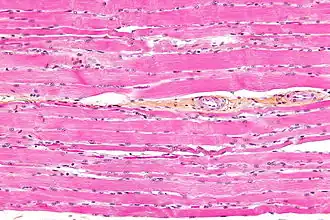

Striated muscle tissue is a muscle tissue that features repeating functional units called sarcomeres. Under the microscope, sarcomeres are visible along muscle fibers, giving a striated appearance to the tissue. The two types of striated muscle are skeletal muscle and cardiac muscle.

Skeletal muscle includes skeletal muscle fibers, blood vessels, nerve fibers, and connective tissue. Skeletal muscle is wrapped in epimysium, allowing structural integrity of the muscle despite contractions. The perimysium organizes the muscle fibers, which are encased in collagen and endomysium, into fascicles. Each muscle fiber contains sarcolemma, sarcoplasm, and sarcoplasmic reticulum. The functional unit of a muscle fiber is called a sarcomere.[2] Each muscle cell contains myofibrils composed of actin and myosin myofilaments repeated as a sarcomere.[3] Many nuclei are present in each muscle cell placed at regular intervals beneath the sarcolemma.

Unlike skeletal and cardiac muscle tissue, smooth muscle tissue is not striated since there are no sarcomeres present. Skeletal muscles are attached to some component of the skeleton, and smooth muscle is found in hollow structures such as the walls of intestines or blood vessels. The fibres of striated muscle have a cylindrical shape with blunt ends, whereas those in smooth muscle are spindle-like with tapered ends. Striated muscle tissue has more mitochondria than smooth muscle. Both smooth muscle cells and cardiac muscle cells have a single nucleus, and skeletal muscle cells have many nuclei.[6]